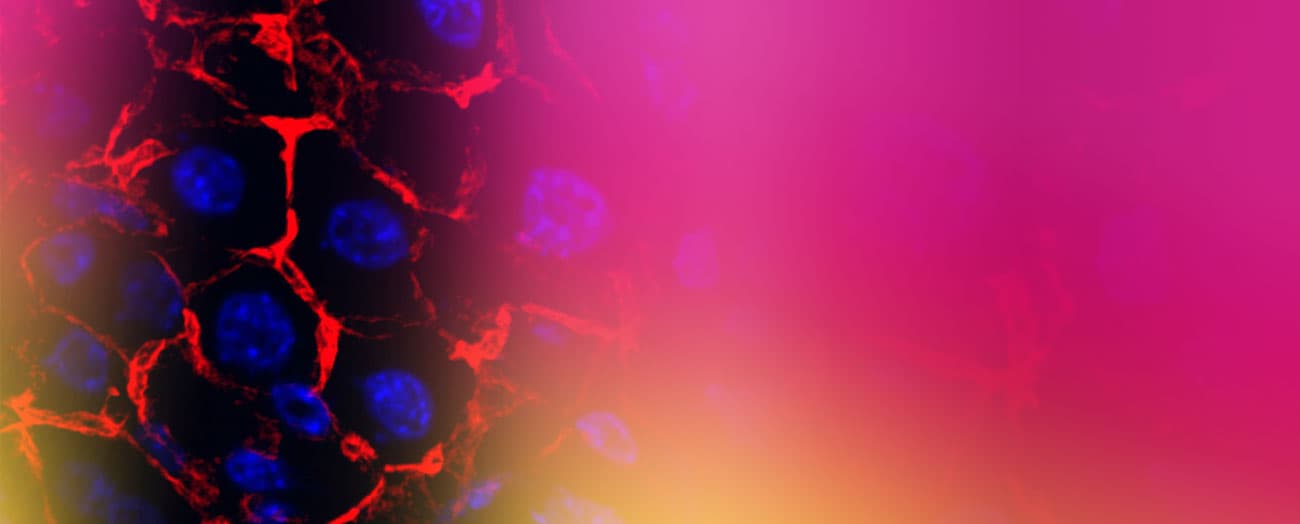

Image Gallery

Research images from the Pradhan-Sundd laboratory at Versiti Blood Research Institute.